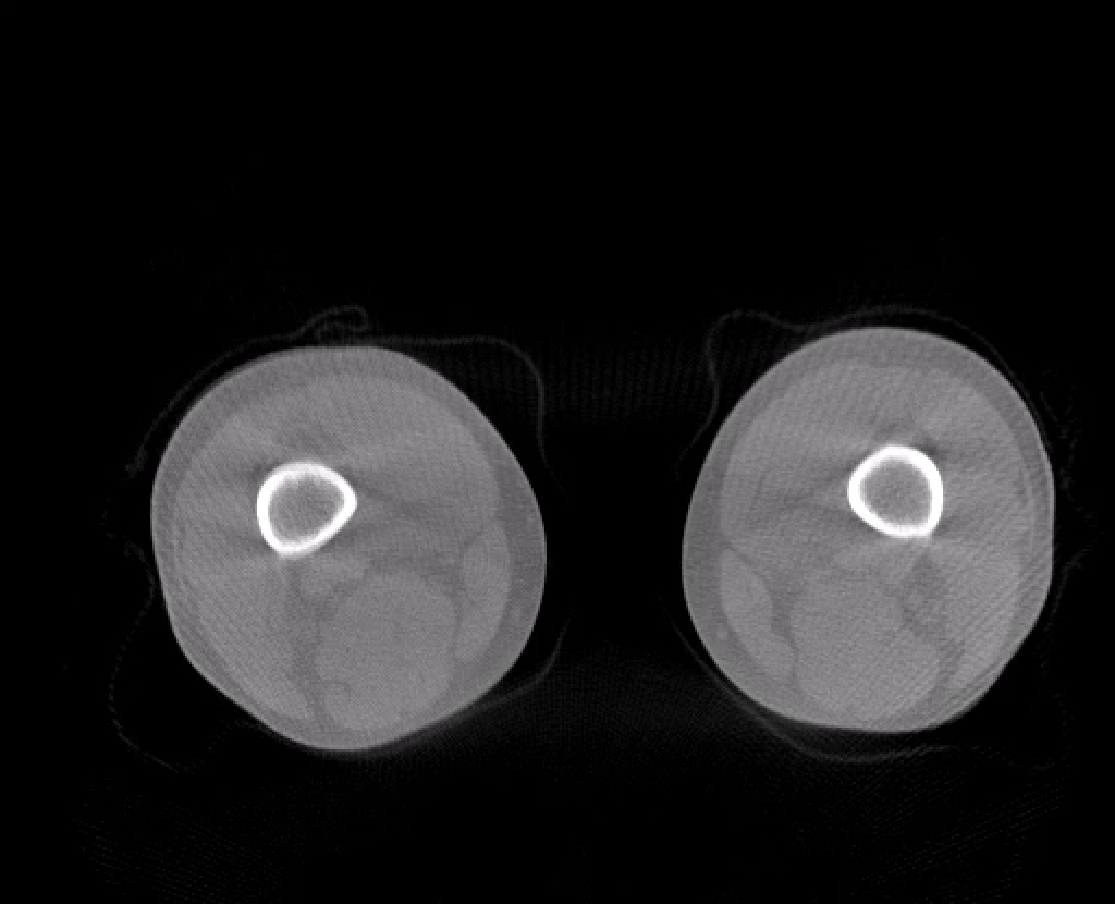

负重位状态下WR-3D MPR多平面重建

负重位状态下WR-3D断层重建图像